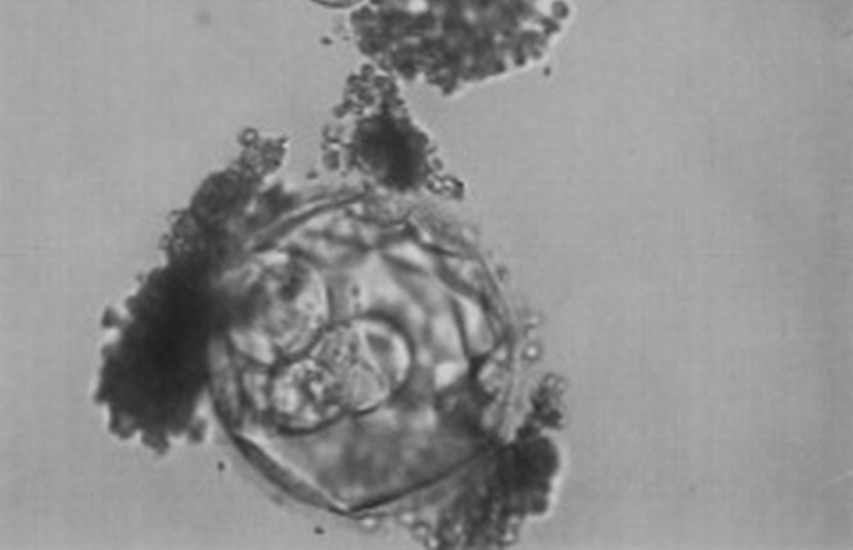

W trakcie sztucznego zapłodnienia człowiek zostaje powołany do życia nie w łonie matki, lecz w warunkach laboratoryjnych. Już na samym początku istnienia ma więc dużo gorsze warunki do rozwoju, niż człowiek poczęty w sposób naturalny. Żadne sztuczne podłoże nie jest w stanie zastąpić naturalnego środowiska organizmu kobiety.